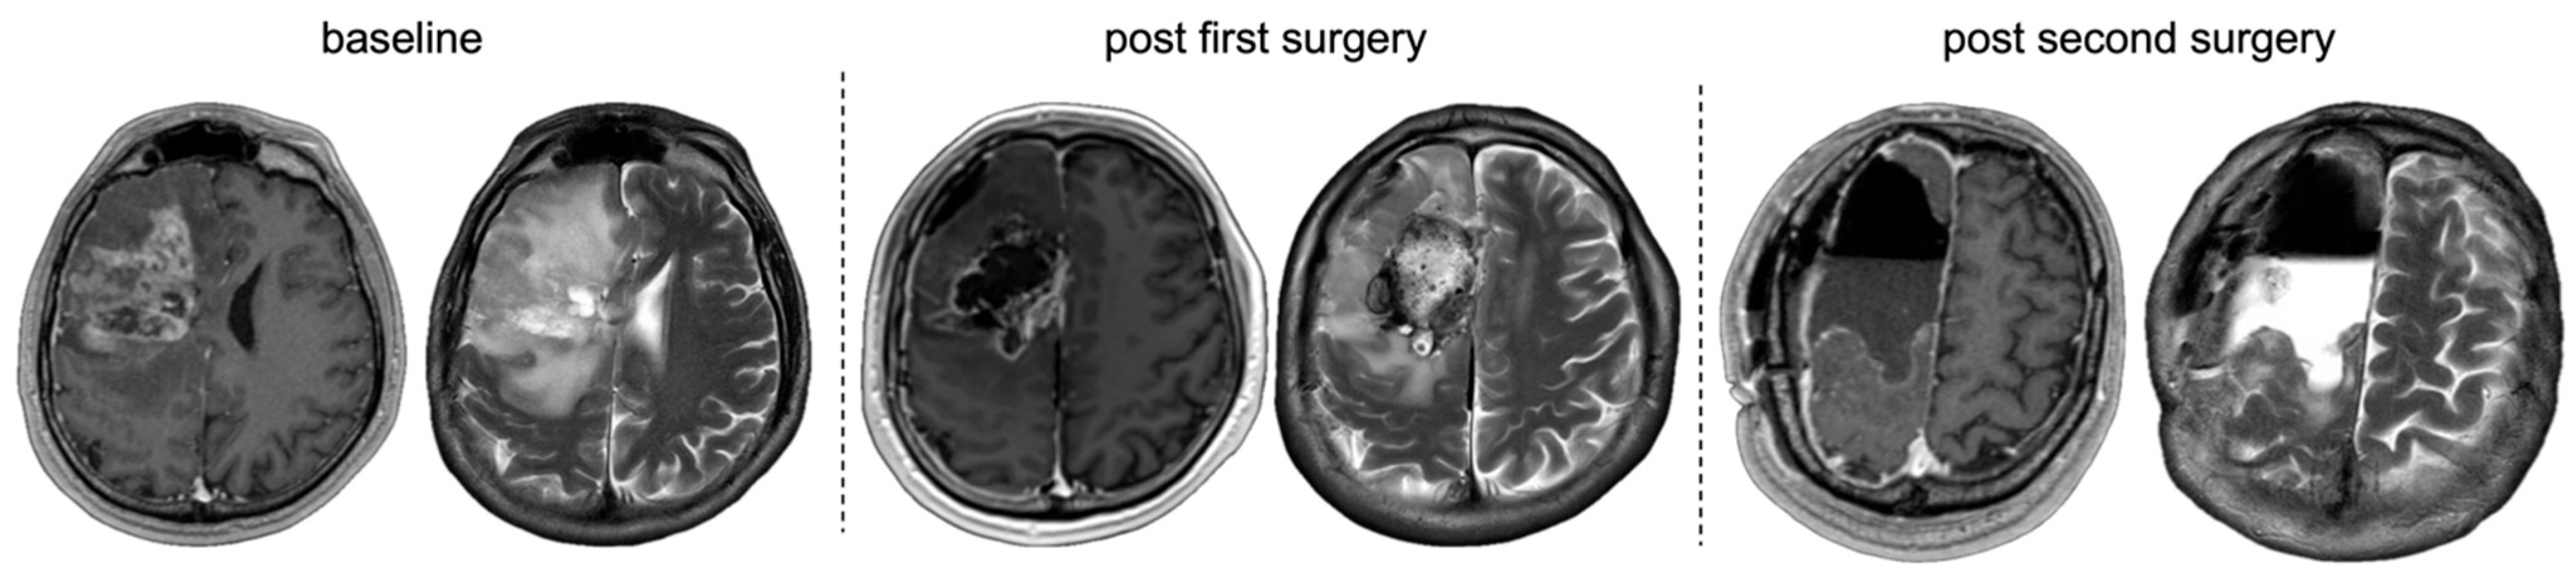

3.5.1. Multifocal Approaches